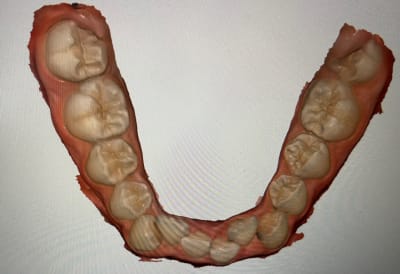

On peut avoir une photo mandibulaire vue du dessus ?

Le repositionnement incisif bas est marqué non ? Je me tate à te dire d'envisager une incisive mandibulaire . Le milieu est comment ?

Voir le bas, le niveau d'encombrement.

Les incisives sont bien lingualées oui je pense qu’on peut jouer un peu dessus pour procéder à l’alignement et éventuellement en effet réévaluer en cours du traitement et si besoin extraire une incisive inférieure ?

Pas de vue occlusal mand ? Ouvre medit link et sors nous une vue occlusale. Ne surtout pas extraire une incisive mandibulaire. Tu vas augmenter la supraclusion et créer un overjet.

Et oui n'extrait pas en bas à la vue de ta photo mandibulaire stp et la supra actuelle.